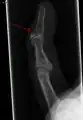

El diagnóstico generalmente se basa en el estudio de los síntomas, apoyado por Radiografías .

La radiografía que muestra fractura en la inserción del tendón extensor